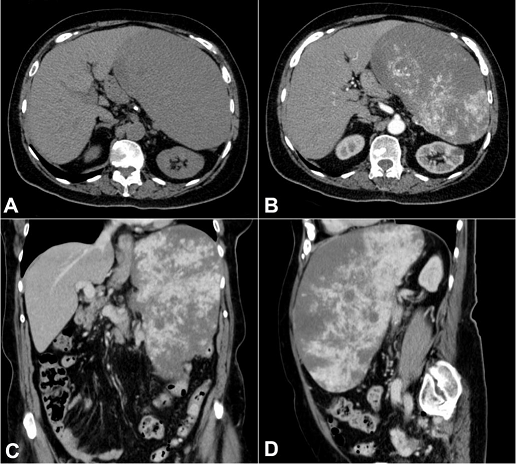

An 80-year-old woman was admitted with a 6-month history of progressive abdominal pain, weight loss, fatigue, and pallor. Her past medical history included hypertension and atherosclerotic cardiovascular disease. The physical evaluation was generally unremarkable except for massive splenomegaly and pallor. The spleen edge was palpable 10 cm below the left costal margin, firm, and painless. There was no palpable lymphadenopathy. The laboratory work-up showed anemia (hemoglobin was 8.9 g/dL; reference range [RR]: 12.3–15.3 g/dL) with mild microcytosis (MCV = 79.3 fL/red cell) and 1.36% of reticulocytes. The white blood cell and platelet counts were within the reference range and distribution. Renal and liver function test results were in the reference range with a ferritin level of 206 ng/mL (RR: 13–150 ng/mL) and transferrin saturation of 10% (RR: 20%–50%). The folic acid and vitamin B12 determinations were unremarkable. An abdominal computed tomography (CT) scan revealed a 24 × 11 × 18 cm diffusely heterogeneous spleen with hypovascular areas with a volume of 2470 mL (RR: 107.2–314.5 mL). The liver was unremarkable, and no evidence of venous thrombosis or abdominal lymphadenopathy was found ( Figure 1).

Chest CT scan suggested cardiomegaly and coronary atherosclerotic disease. Upper digestive endoscopic evaluation revealed a small gastric polyp, which was revealed to be a foveolar polyp. A bone marrow biopsy disclosed an increased population of the three cellular lineages for the patient’s age; approximately 60% cellularity with increased granulocytic precursors, suggestive of retarded maturation, including 1% of CD34 immature cells. There was no morphological evidence of lymphoma and no reticulin fibrosis. The patient was discharged and referred to an outpatient clinic follow-up with the working diagnosis of splenomegaly secondary to myelodysplastic syndrome. One week later, the patient returned to the emergency room complaining of acutely worsening abdominal pain. There was no history of trauma before the onset of symptoms. Physical examination showed hemodynamic instability (mean arterial pressure of 57 mmHg, pulse rate of 86 bpm), with marked pallor, and diffuse abdominal tenderness. Laboratory studies revealed a hemoglobin value of 5.7 g/dL with mild microcytosis (MCV = 79.1 fL/red cell) and leukocytosis. The platelet count and renal and liver functions remained in reference ranges. Serologic studies for HIV, hepatitis B, and C, and syphilis were negative. After clinical stabilization and packed red blood cell transfusion, a point-of-care ultrasound revealed free intraperitoneal fluid. The abdominal CT scan confirmed mild hemoperitoneum attributable to spleen rupture and an emergency laparotomy with splenectomy was performed. The postoperative period was uneventful, and the patient was discharged after 6 days of hospitalization. Two months after discharge, the patient was re-evaluated and the CT images showed metastases in the liver and peritoneum.